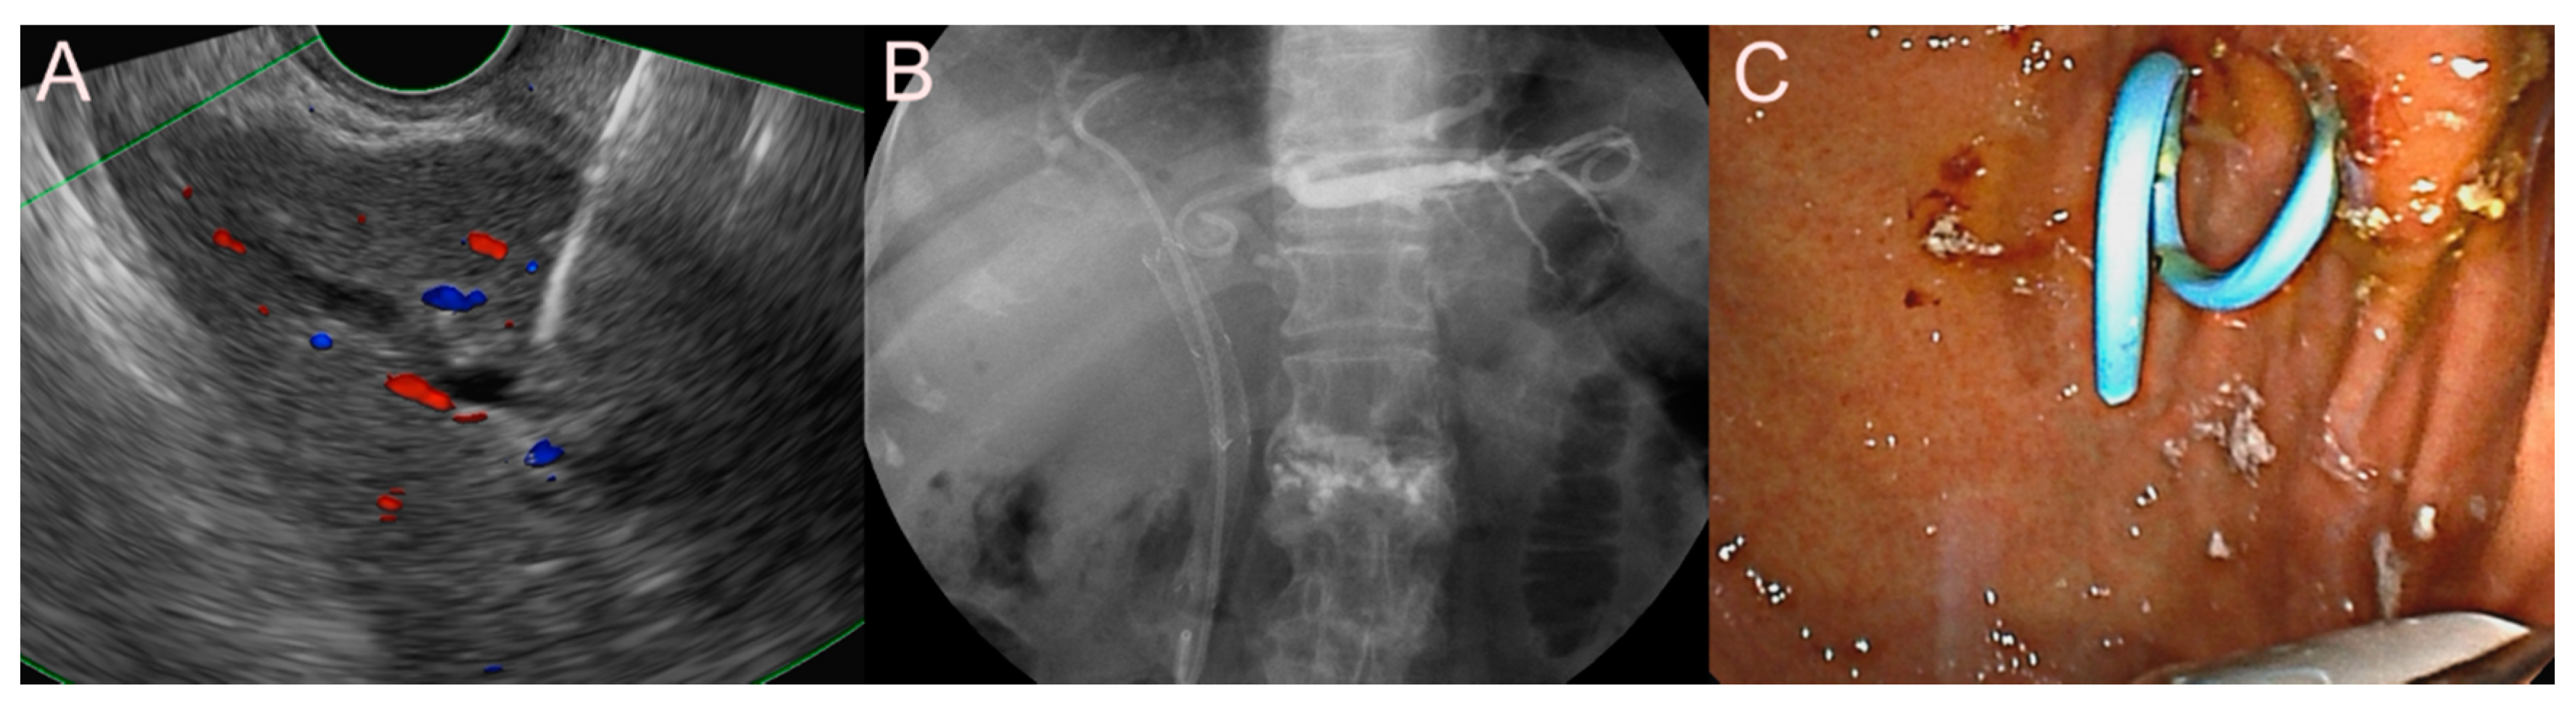

2.5. Stent for EUS-Guided Creation of Entero-Enteric Anastomosis